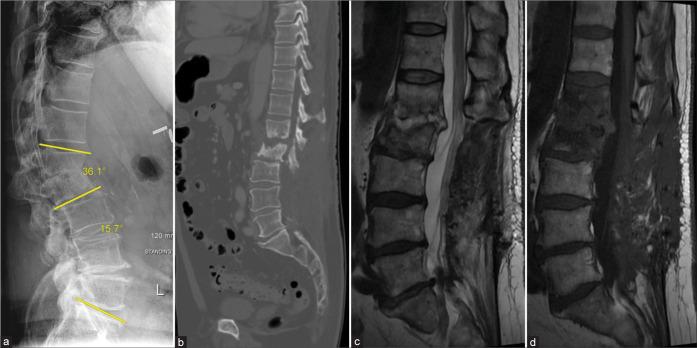

A 77-year-old male presented with L1-2 TB osteomyelitis secondary to intravesical BCG application. A 36.1° focal nonfixed kyphotic deformity was evident on standing X-rays that reduced in the supine position. He underwent posterior percutaneous screw fixation with rods extending from the T12 to L3 levels, with resolution of his mechanical pain. Nine months later, the CT demonstrated reconstitution of the vertebral bodies (i.e., volume increase of 6.99 cm (21%) and 7.49 cm (27%) at L1 and L2, respectively). Standing X-rays after hardware removal demonstrated 32.7° of lumbar lordosis and a reduction of focal kyphosis to 12.9°.

一名77岁男性因膀胱内应用卡介苗继发L1-2节段结核性骨髓炎。站立位X线片显示明显的36.1°局灶性非固定性后凸畸形,仰卧位时畸形减轻。他接受了从T12至L3节段的后路经皮螺钉固定及棒植入,机械性疼痛得到缓解。9个月后,CT显示椎体重建(即L1和L2椎体体积分别增加6.99 cm(21%)和7.49 cm(27%))。取出内固定后的站立位X线片显示腰椎前凸为32.7°,局灶性后凸畸形减轻至12.9°。